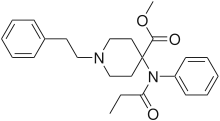

Anilidopiperidines